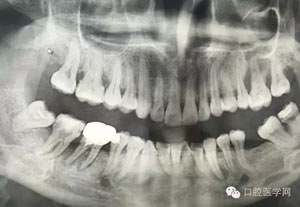

病例1:患者迫切希望保留自己的這一顆牙齒,根尖周陰影比較大,二度松動.而且旁邊有種植修復體,和患者溝通好后,治療好后觀察一個月后冠修復,因為有種植的后期修復,所以有了機會觀察,術后三個月和術后四個月,根尖恢復的還算不錯,希望能夠繼續觀察下去.這樣子的病例,做的時候我們一定要非常的小心,和患者要有充分的溝通以及不同科室的溝通然后決定怎么樣做比較好,假如就是出現了問題,到時候我們也比較好處理些,免得我們自己到時候不好收場。

24.jpg

25.jpg

26.jpg

27.jpg

28.jpg